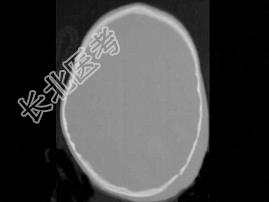

- 单项选择题男,3岁, 头颅被球击中,请结合CT图像, 选择最可能的诊断是  (    )

A、高血压性脑出血

B、脑结核

C、脑挫裂伤血肿形成

D、动脉瘤破裂出血

E、血管畸形